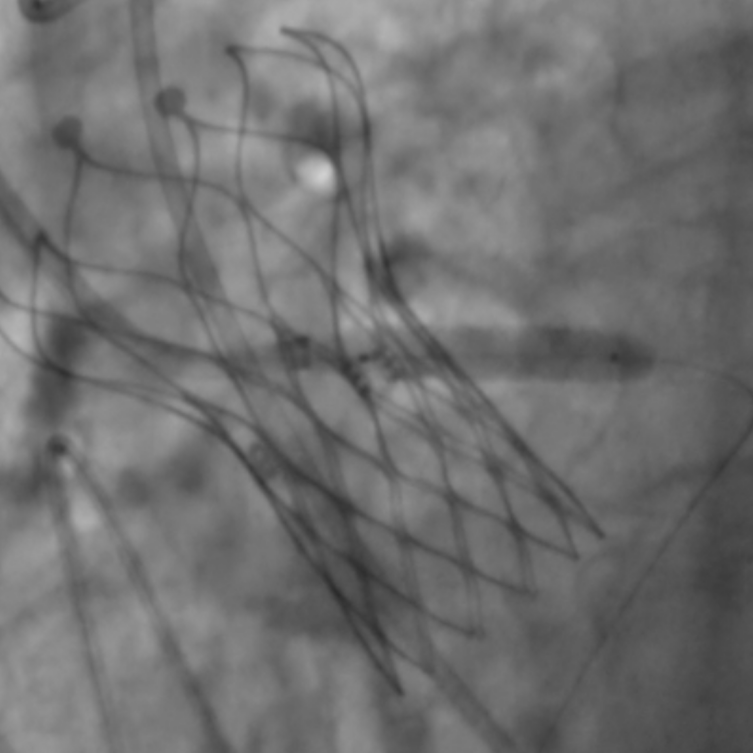

左冠植入4.0x19mm冠脉开窗支架

图片

5.0mm球囊后扩张支架近段

复查左冠开口面积恢复至12.76mm2

经主动脉路径植入14mm-16mm PDA封堵器